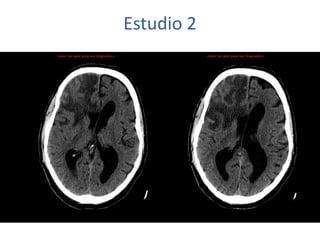

Estudio 2

• Estudio sin y con contraste, con reconstrucciones sagitales y coronales

del estudio con contraste.

Se observa una lesión ocupante de espacio en lóbulo frontal derecho que

presenta un tamaño de 18 x 32 x 22 mm (cc x ap x tr), bilobulada, no del

todo bien delimitada, con realce en anillo irregular, con hipocaptación

central, probablemente por necrosis, y asociada a un extenso edema

vasogénico con efecto masa tanto sobre los surcos de la convexidad

como sobre la cisterna insular, el sistema ventricular y la línea media,

esta última con un desplazamiento de 5 mm a la altura del septo

interventricular.

No se aprecian otras lesiones focales intra o extraaxiales de significación

patológica.

Habría que considerar como primera posibilidad que se tratase de una

lesión metastásica, por bien un tumor primario, aunque no se puede

descartar otras opciones, sin imprescindible correlación con la clínica y

con sus antecedentes.